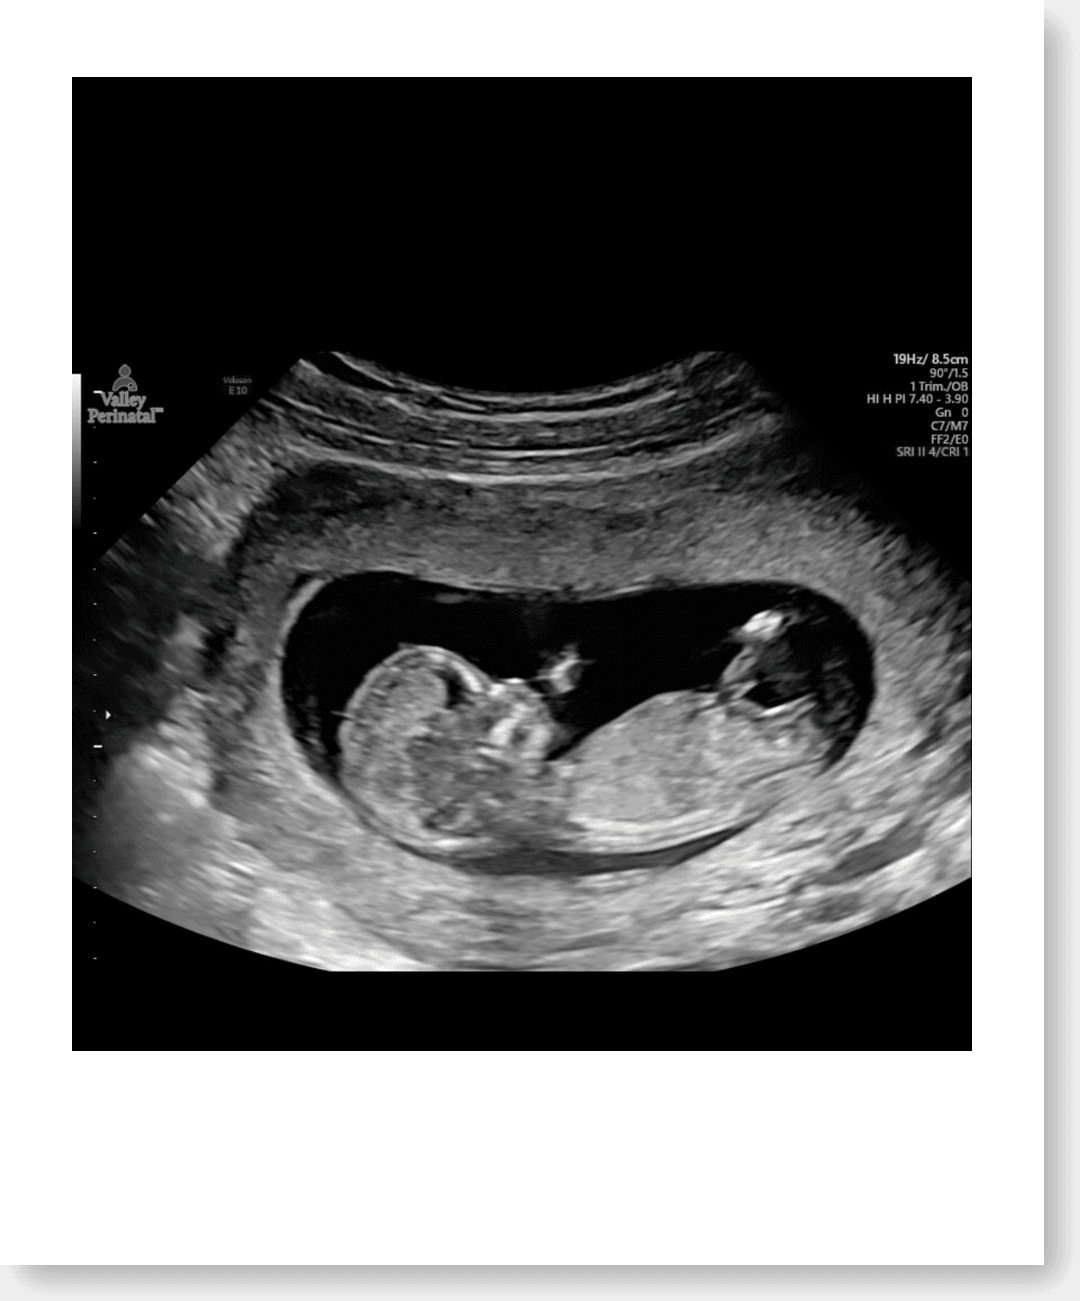

Baby King ultrasoundComing January 2026 🍼